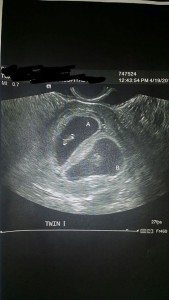

We did IVF and the afternoon before our 6-week ultrasound I started bleeding. I already had 1 early miscarriage so I thought the worst. The next morning we went in for the ultrasound and our infertility doctor came in the room and took out “the wand” and started. I held my breath and prayed. He said, “OK, so I’m seeing 3 sacs… which means triplets…” I looked at my husband and I’ve never seen him so scared in his entire life!!! Then in the next breath our doctor said, “Wait a minute — no, that one is a blood clot, which explains the bleeding. So you’re having twins!” I looked back at my husband and you’d think he was just found not guilty of murder! He was so relieved! And so was I. Twins we were mentally prepared for. I burst into tears and laughter and he looked like he was about to pass out. It was a great moment; finally getting our babies!!!

My first ultrasound was spur of the moment. It was my first appointment to see if I was in fact pregnant. When I was indeed my OB said to do a scan right then and there due to a previous ectopic pregnancy resulting in my fallopian tube being removed. So of course I was alone. When they did it there were 3 sacs. I almost fell off the table. My first thought was, “My husband’s going to kill me, or have a heart attack, or both!” LOL! When I told him (after a very long day at work) He said, “You’re joking.” He didn’t believe me until I showed him the ultrasound pic. For the next six weeks all you heard him say was, “Triplets… jeez…” One sac never developed so we ended up with twins.